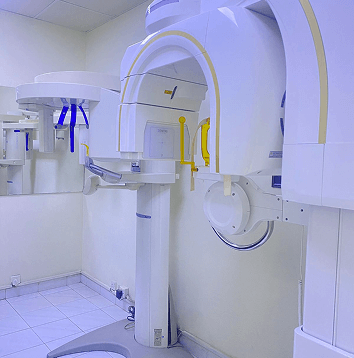

Building Your Perfect Smile: The Blueprint for Modern Dentistry

Consider a master planner constructing a new building. He would not go about it without a very specific blueprint, right? Today, in dentistry, we feel that your smile deserves the same kind of detail. At Altamash Dental Clinic, it is here that CBCT treatment planning comes into play. It is not only a diagnostic tool; [...]

The Future of Your Smile: Where Dentistry Meets Modern Technology

It should come as no surprise that technology is revolutionizing healthcare, and dentistry is no different.